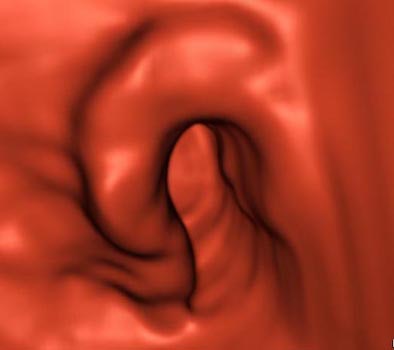

![]() |

| Three-dimensional MDCT endoluminal view shows the morphology of the stenosing lesion with excellent detail. Image courtesy of Dr. Riccardo Iannaccone. |